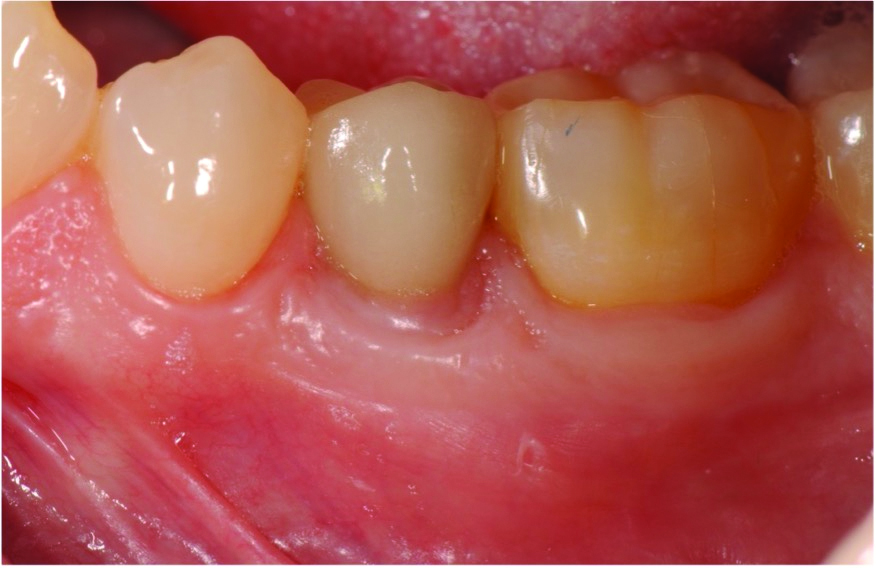

A postsurgical periapical x-ray was taken (Figure 9). Postoperative visits were at 2- to 3-week intervals. The patient was instructed to use chlorhexidine for 2 weeks, followed by the use of a two-row soft toothbrush and interproximal flossing. Interproximal proxy brush usage began after the suture removal at 4 weeks. After 2 months, healing was excellent (Figure 10); at 9 months, the interproximal papillae regeneration was complete, and radiographic confirmation of radiographic intrabony defect fill was observed (Figure 11 and Figure 12). After 1 year, maintenance visits were conducted by the restorative office's registered dental hygienist.

Six-year and 11-year recall visits (Figure 13 through Figure 15) confirmed stable long-term soft- and hard-tissue regeneration and bone healing.

Fig 10. Clinical presentation at 2-month follow-up.

Figure 10

Fig 14. Clinical presentation at 6-year recall showing stable results.

Figure 14